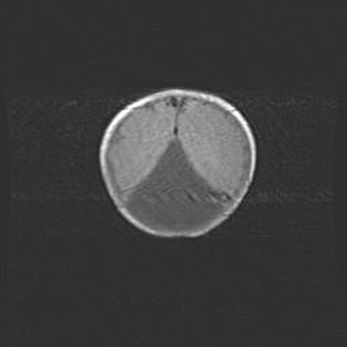

Множественные мелкие кисты перивентрикулярной области.

Киста прозрачной перегородки.

Возраст: 28 дней

Вес: 2400 г

Пол: женский

Окружность головы: 33 см

Срок гестации: 34 недели

Перивентрикулярная киста – это полостное образование в околожелудочковых областях белового вещества головного мозга. С морфологической точки зрения – это мелкоочаговая зона коагуляционного некроза, возникшая после инфаркта белого вещества. Наиболее часто поражаются начальные отделы задних рогов боковых желудочков. Обычно образования заполнены жидкостным содержимым.

Киста прозрачной перегородки может располагаться в переднем отделе межжелудочковой перегородки, в области мозолистого тела и мозжечка.